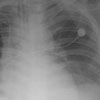

The patient is acutely hypotensive and tachypneic. He has generalized tenderness and moderate distention of the abdomen. A central venous catheter is placed for aggressive fluid resuscitation, and a chest film is obtained.

What abnormality is evident on this radiograph-and what further action is warranted?

Pneumoperitoneum

The chest radiograph revealed subdiaphragmatic free air (arrow),which prompted immediate surgical consultation.